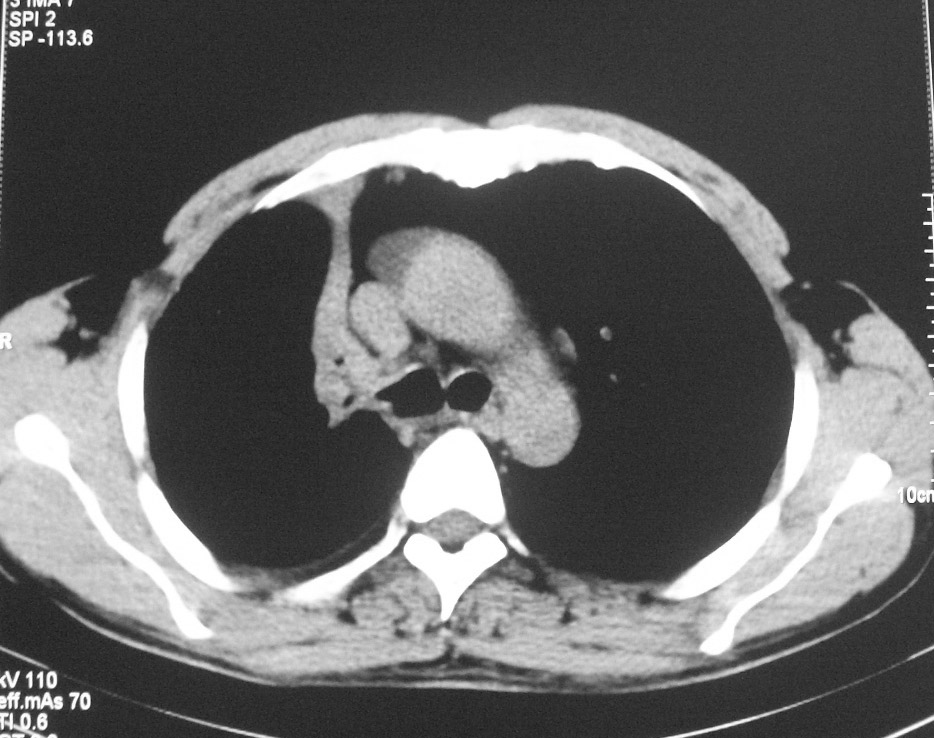

标题: CT5485:[原创]肺部占位请讨论

左肺上叶不张,左肺上叶支气管狭窄,呈鼠尾征,左侧胸腔内见少许积液,考虑左肺上叶中心型肺伴左侧胸腔内少许积液可能,不除外结核,建议支气管镜检查.

左肺上叶不张,可见软组织肿块,左肺上叶支气管狭窄,呈鼠尾征,左侧胸腔内见少许积液,纵隔内未见肿大淋巴结,建义做个增强或支气管镜

左肺上叶不张,左肺上叶支气管狭窄,呈鼠尾征,左侧胸腔内见少许积液。

考虑:1、左肺上叶中心型肺伴肺不张、左侧少量胸腔积液;

2、可疑纵隔淋巴转移;

3、建议支气管镜检查。